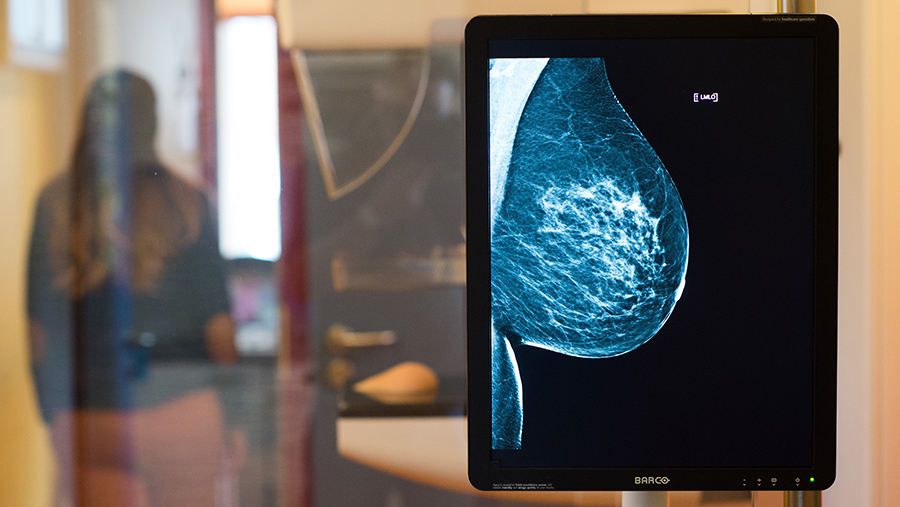

Маммолог перечислил находящиеся в зоне риска по раку груди группы населения

Фото: TASS/Klaus-Dietmar Gabbert

Риск развития рака молочной железы высокий у пациентов с отягощенным семейным анамнезом, рассказал в интервью «Известиям» заместитель главного врача онкологии МКНЦ им. А.С. Логинова Гурами Кветенадзе.

«То есть у тех, у кого в роду были онкологические заболевания», — уточнил врач.

Также, по его словам, в группе риска по раку груди находятся пациенты, у которых выявлены генетические мутации в генах BRCA1 и BRCA2, влияющие на образование рака молочной железы и рака яичников.

«Их организм уже при рождении был запрограммирован на то, что в течении жизни проявится онкологическое заболевание», — подчеркнул он.

Гурами Кветенадзе уточнил, что 30% случаев впервые выявленного рака молочной железы носит наследственный характер.

Также, по словам врача, высок риск развития рака молочной железы у женщин зрелого возраста — 50 лет и старше.

Маммолог рекомендовал с 40 лет раз в два года делать маммографию и ультразвуковое исследование. А по достижении 50 лет проходить эти обследования раз в год.

При этом он отметил, что, если пациент находится в группе риска, для него подбирается индивидуальная программа наблюдения, позволяющая своевременно выявить заболевание и успешно его вылечить.

Подробнее читайте в эксклюзивном интервью «Известиям»:

«Пятилетняя выживаемость пациентов при первой стадии составляет 95–98%»